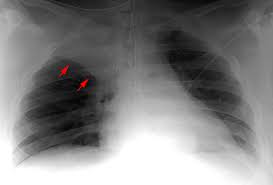

Dugaan adanya atelektasis didasarkan dari gejala-gejala yang ada dan hasil pemeriksaan fisik. Diagnosa bisa dipastikan dengan melakukan pemeriksaan foto sinar-x dada. Terkadang bisa dilakukan CT scan dada, bronkoskopi, atau keduanya untuk menemukan penyebabnya.

Sumber : http://www.radiologyschools.com